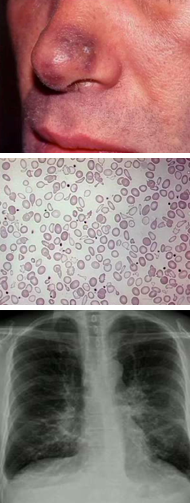

A 68 year old patient with HIV has CD4 count of 100 and a viral load of 100. He has had HIV for 30 years. He has the skin lesion below, chronic cough and fatigue. His peripheral blood smear and CXR are shown below. What is causing his symptoms?

Visceral Kaposi sarcoma in the GI and respiratory tracts. Note the hypochromatic RBCs indicating iron-deficiency anemia from GI blood loss.